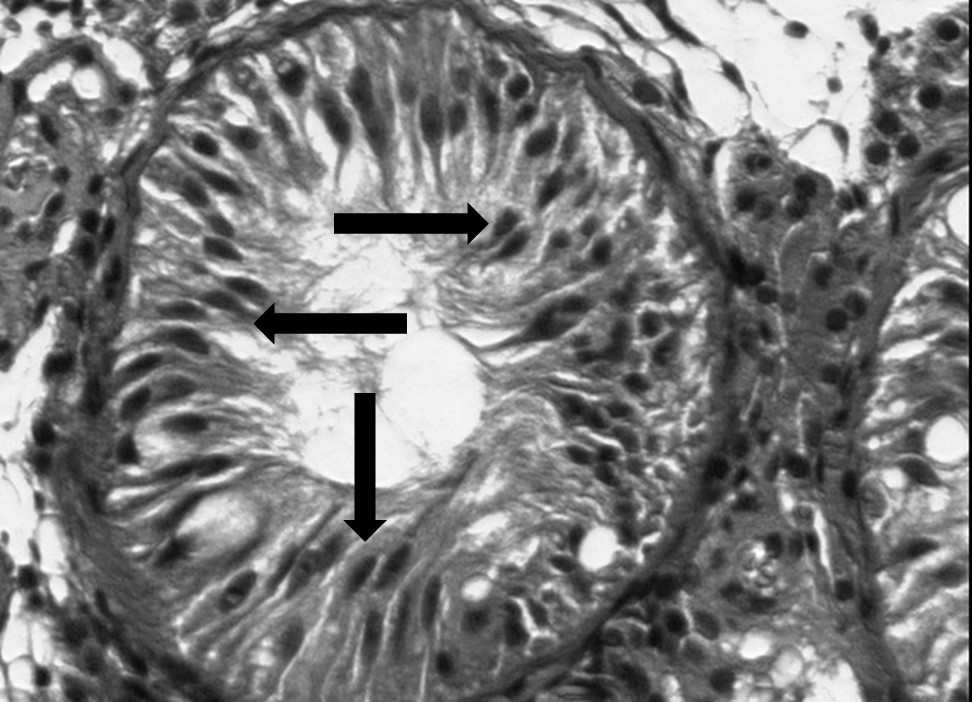

This is a cross-section of a seminiferous tubule. Which cells do the arrows point to?

2.

3.